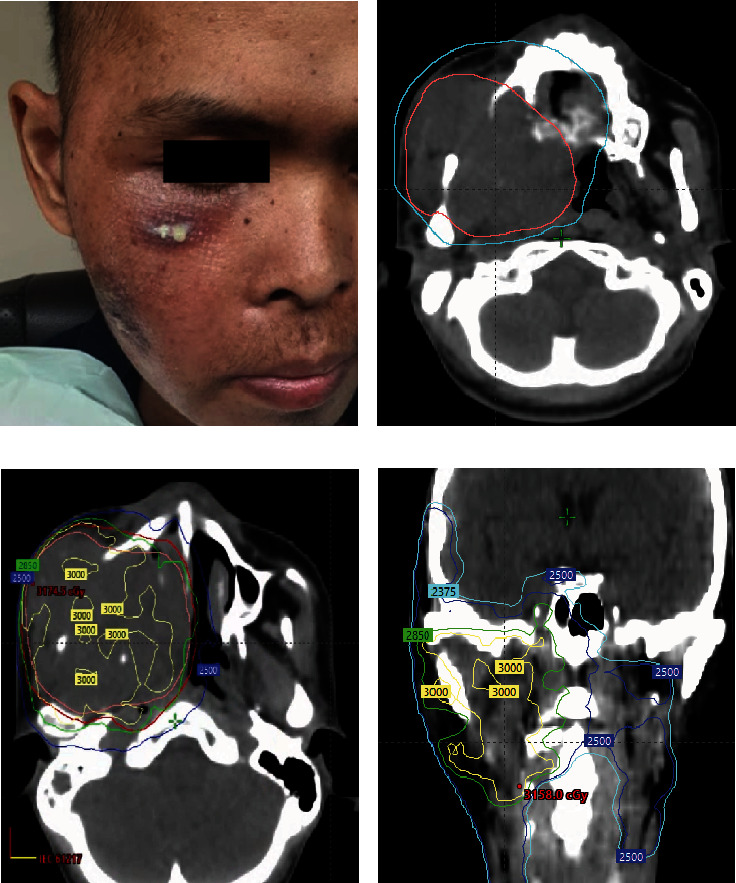

Sinonasal malignancies (SNMs) are rare heterogeneous malignancies that frequently present with locally advanced disease. The prognosis is poor when the disease is considered extensive and unresectable. In such cases, a high-dose palliative radiotherapy regimen is often required, but the ideal dose and fractionation have not been established. We detail a 33-year-old male who initially presented with a progressively growing mass over the right cheek. A biopsy of the lesion revealed squamous cell carcinoma (SCC). Imaging revealed a very advanced and unresectable disease with the involvement of several head and neck subsites. He progressed further after receiving induction chemotherapy from an outside institution. The patient requested prompt tumor and symptom control to travel back to his home country. We offered him high-dose split-course palliative radiotherapy in the form of a quad Shot of 14.80 Gy in four fractions twice daily, followed by 30 Gy in five fractions every other day with a 2-week interval. Treatment resulted in excellent clinical response with symptomatic relief in a short time, and the patient could travel back home safely.